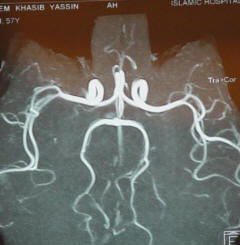

MRI of the brain with contrast with MRA of the brain and carotids and MRI of the cervical spine were performed 31-March-2010 demonstrating old scattered infarction both cerebral hemispheres with recent infarction in the left hemisphere near the internal capsule and the GPI. The vascular system was normal except for narrowing of the left vertebral artery at its origin. The cervical spine showed only the old malacia changes, which were noted before surgery. The usual artifacts were noted due to implants, but it was possible to see that the spinal cord has no major morphological changes.

Absent both Posterior Communicating  arteries provoking the insult.

In retrospective analysis after this case, more than 100 of several patients were evaluated for MRA data  for the presence of the PcoAa  performed in 1.5 tesla and some of 3 tesla MRI machines available in the market. It was found that, it is missing in all of them. The AcoA was found in 43% of them. This means that the MRA data are not realistic for evaluation of the true situation. This means that our case and the above mentioned author came to the wrong conclusion and other causes must be sought. These data also trigger the requirement to improve the realistic quality of the MRA data or to perform angiography so as not make these misinterpretations. 27-May-2010.